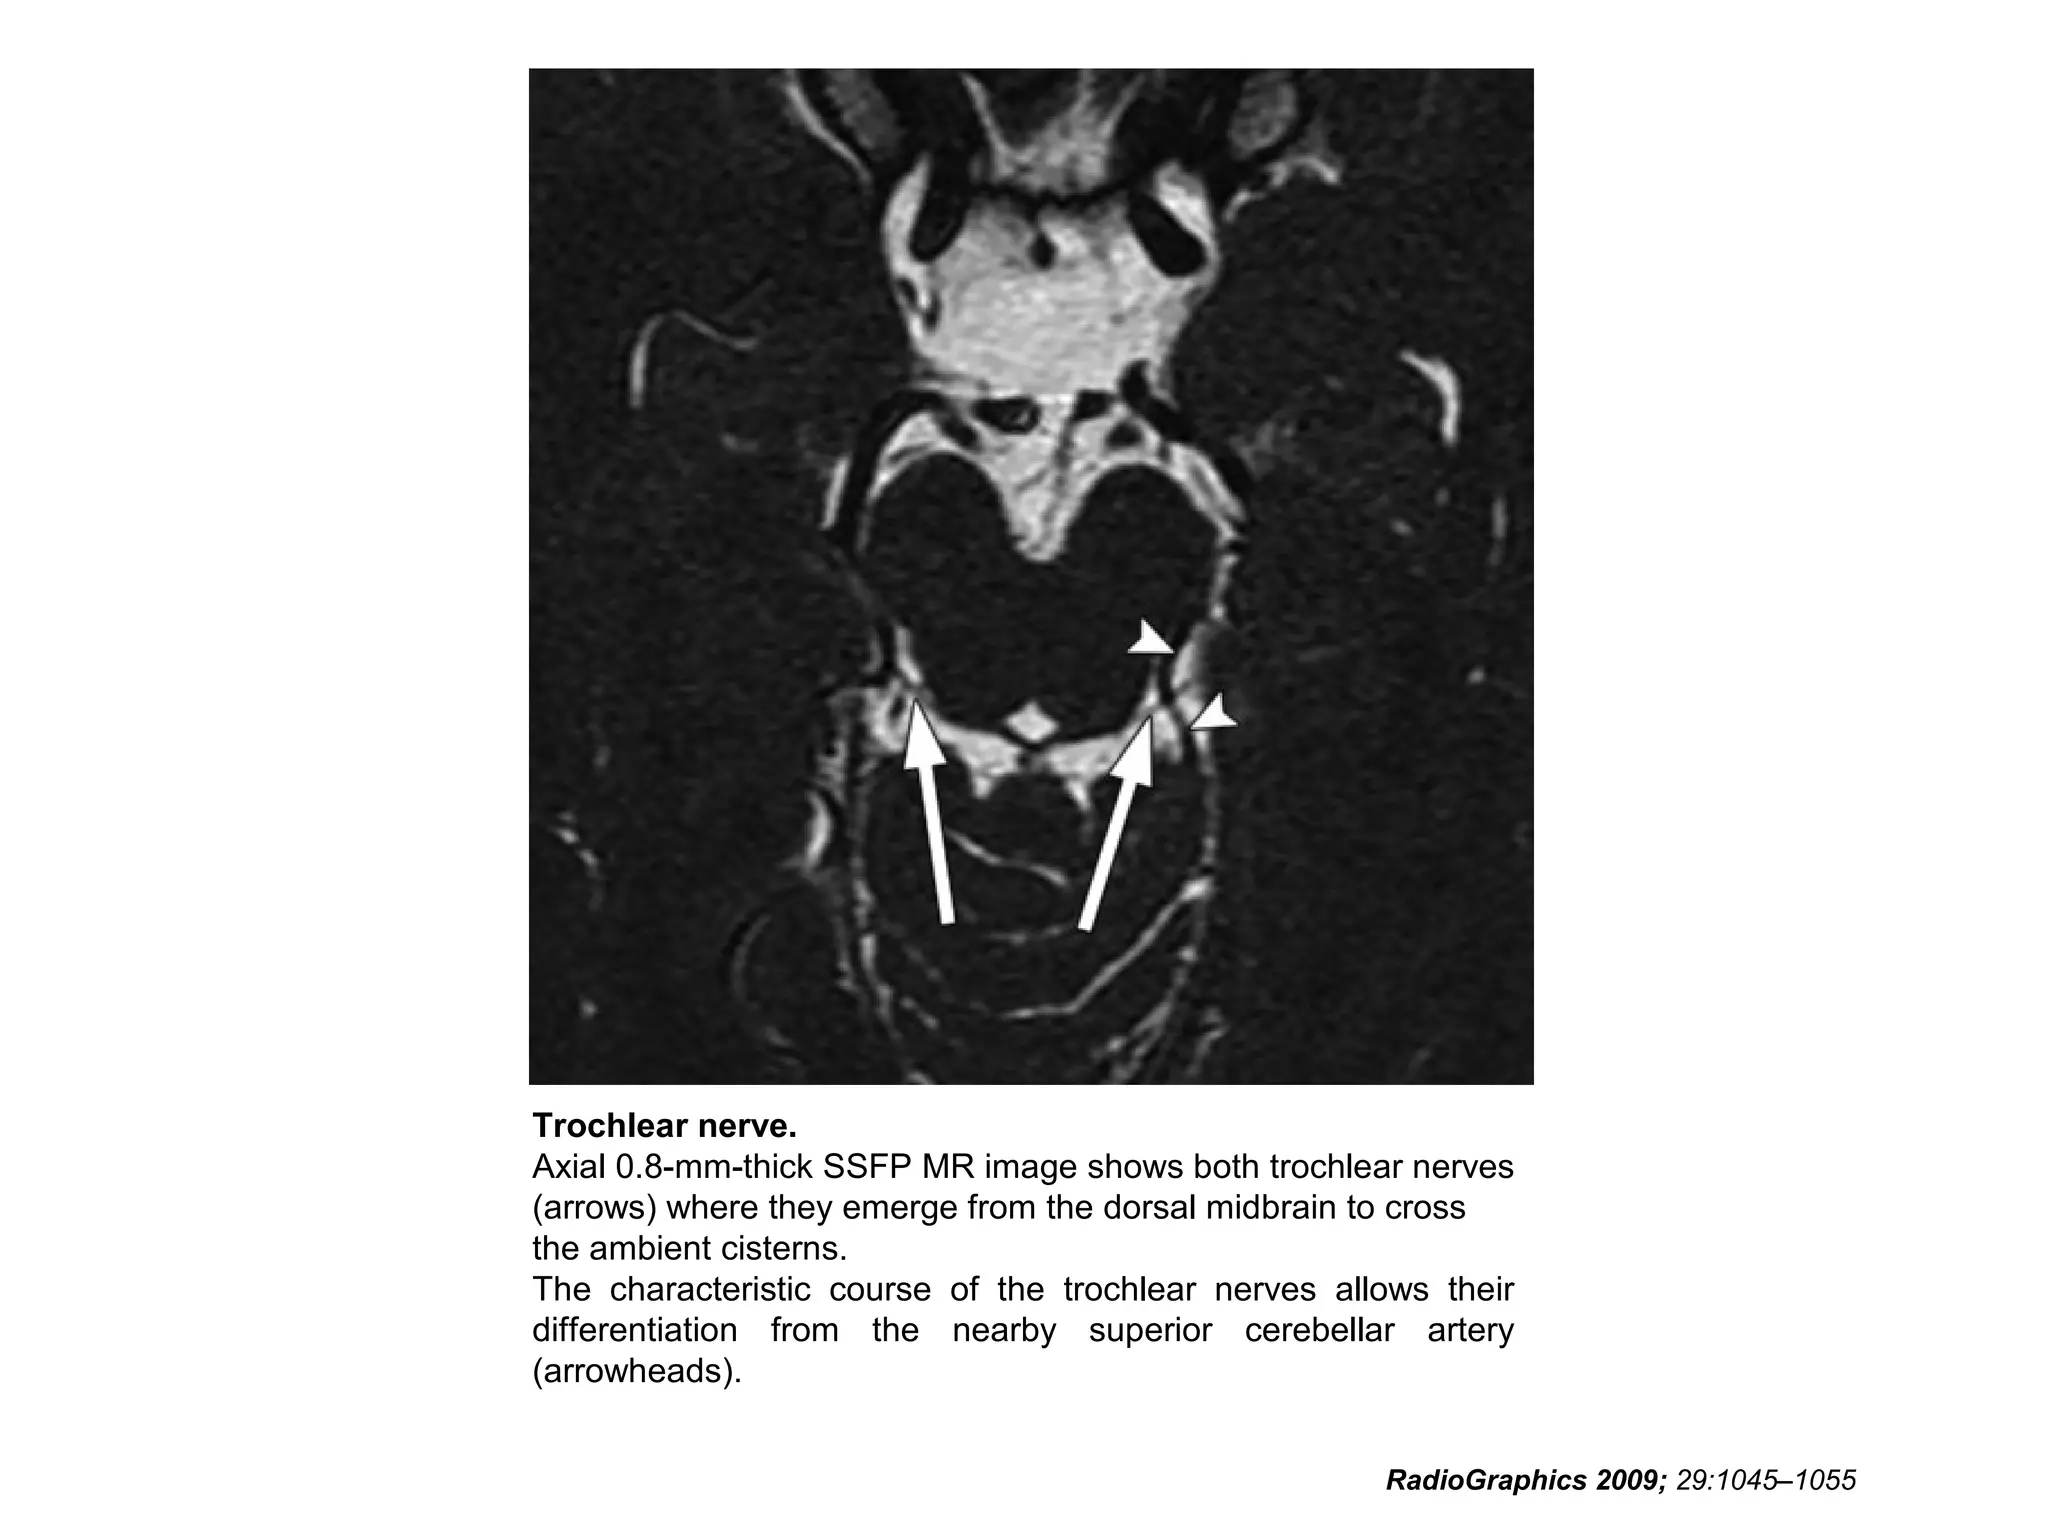

Cranial Nerve IV:

The Trochlear Nerve

• The trochlear nerve is the only nerve with a root

entry zone arising from the dorsal (posterior)

brainstem.

• After exiting the pons, the trochlear nerve curves

forward over the superior cerebellar peduncle,

then runs alongside the oculomotor nerve

between the posterior cerebral and superior

cerebellar arteries.

• The trochlear nerve then pierces the dura to

enter the cisterna basalis between the free and

attached borders of the cerebellar tentorium.

RadioGraphics 2009; 29:1045–1055

• After completing its cisternal course, the

trochlear nerve runs through the lateral

cavernous sinus just below the oculomotor

nerve and enters the orbit through the

superior orbital fissure to innervate the

superior oblique muscle.

• The nerve is named for the trochlea, the

fibrous pulley through which the tendon of

the superior oblique muscle passes.

• The cisternal segment of this tiny nerve is most

easily identifiable posterolateral to the

• Along part of its intracranial course, the trochlear

nerve lies between dural layers, where it is

difficult to visualize on radiologic images.

• Particular attention should be given to the

anterior aspect of the tentorium in patients in

whom the presence of isolated trochlear nerve

palsy is suspected.

Trochlear nerve.

Axial 0.8-mm-thick SSFP MR image shows both trochlear nerves

(arrows) where they emerge from the dorsal midbrain to cross

the ambient cisterns.

The characteristic course of the trochlear nerves allows their

differentiation from the nearby superior cerebellar artery

(arrowheads).